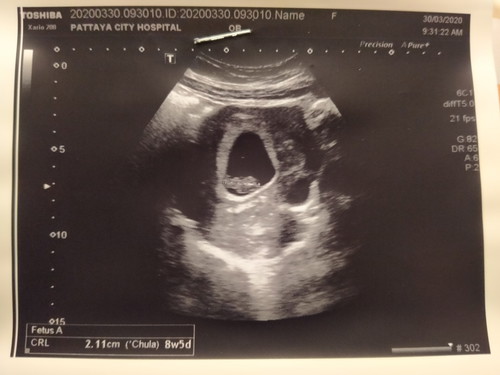

ตั้งครรภ์จะสี่เดือนแล้ว ท้องเล็กมาก ไปซาวด์มาแล้วตอนสองเดือนมีหัวใจน้อยๆเต้นแล้ว อยากรู้แม่ๆคนอื่นท้องเล็กเหมือนกันมั้ย ท้องแรกนะคะ รูปร่างเราไม่ได้ตัวเล็กนะ

โฟกัสที่น้ำหนักน้องคะแม่ถ้าซาวมาน้ำหนักน้องอยู่ในเกณฑ์ก้อไม่มีอะไรต้องกังวล บางคนท้องไม่ออกแต่น้องน้ำหนักดีก้อมีคะ